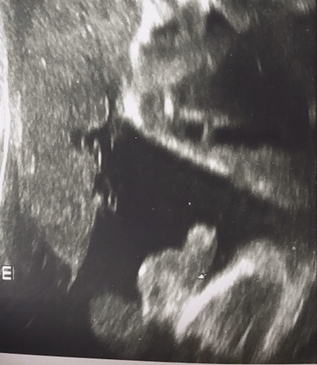

28 недель УЗИ Фотопуз

Сегодня была на узи для себя, меряли кровотоки, все в порядке🙏 Малыш 1284 гр, длина бедренной кости 55мм.

Распечатали фотку наших причиндалов, у нас точно Савелий😂❤️

Есть однократное обвитие пуповины вокруг шейки, мелкий у нас егоза - закрутился таки.